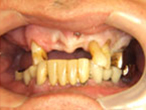

初診時

上下顎に数本の歯が残っていますが咬合支持がほとんどないために満足に食事もできない状態でした。また、下顎前歯部から臼歯部にかけて骨吸収が進行しており、上顎臼歯部にインプラント治療を行うためには骨造成が必要な状態です。

正面